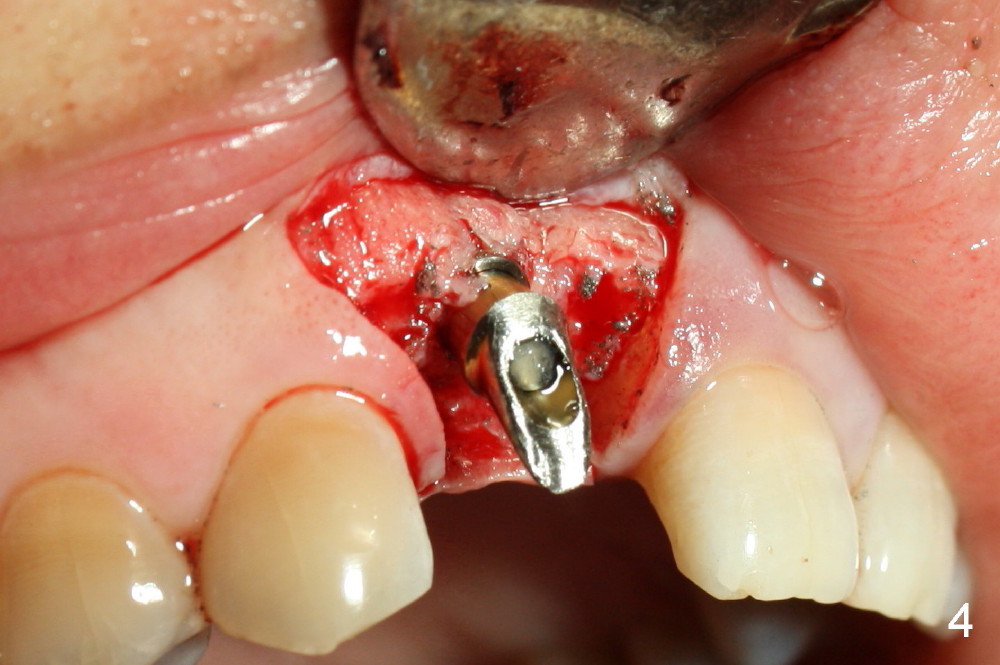

To increase buccal soft tissue bulk, the transverse incision is made lingual to the original socket (Fig.2 *). When the flaps are raised, the alveolar ridge appears to be deviated buccally; the implant (3.8x14 mm, insertion torque ~ 35 Ncm) also looks to be tilted too buccally even though it is placed in the middle of the ridge (Fig.3). An angled abutment (3.9 mm, 25º, 2 mm cuff, Torx A) has been adjusted buccally (Fig.4). The immediate provisional looks long (Fig.5). When the buccal flap is modified (Fig.5 insert) and sutured (Fig.6), the provisional looks to be tilted buccally. A custom Zirconium abutment should be used later on. All of these difficulties are due to delayed implantation with bone atrophy and are avoidable using immediate implant technique. Or check occlusion at the initial stage of osteotomy.